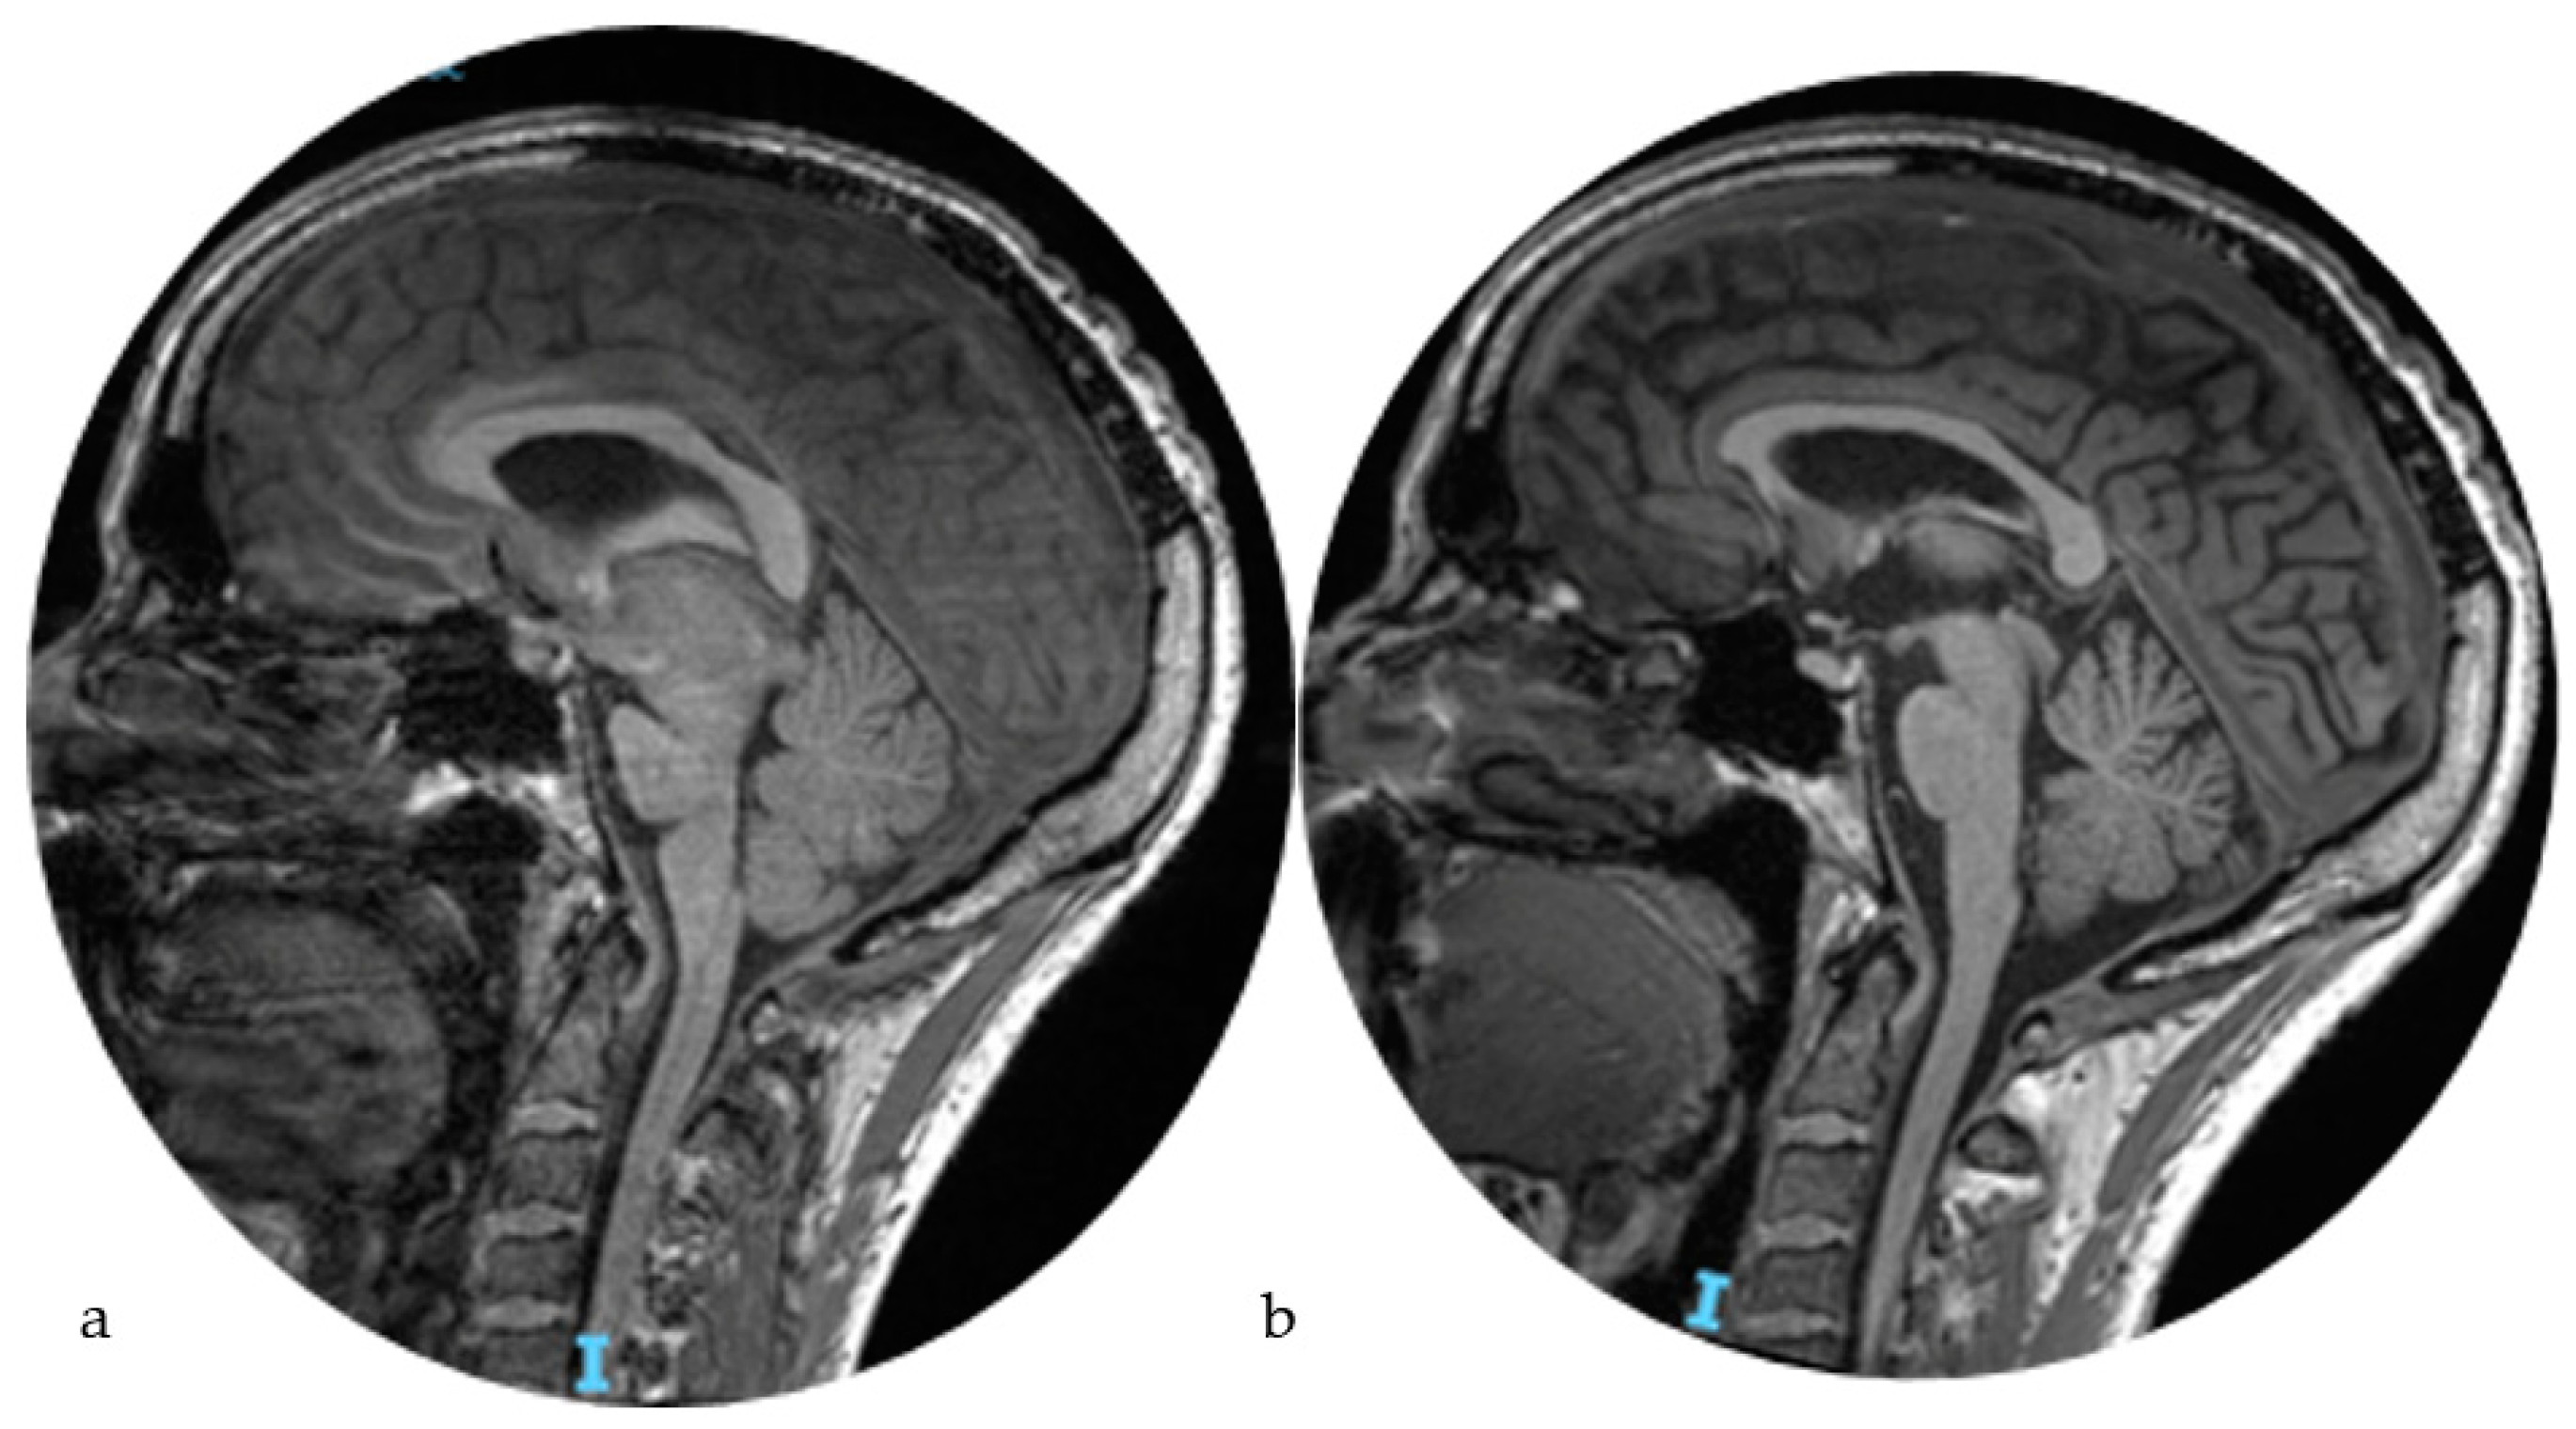

2. Case Report